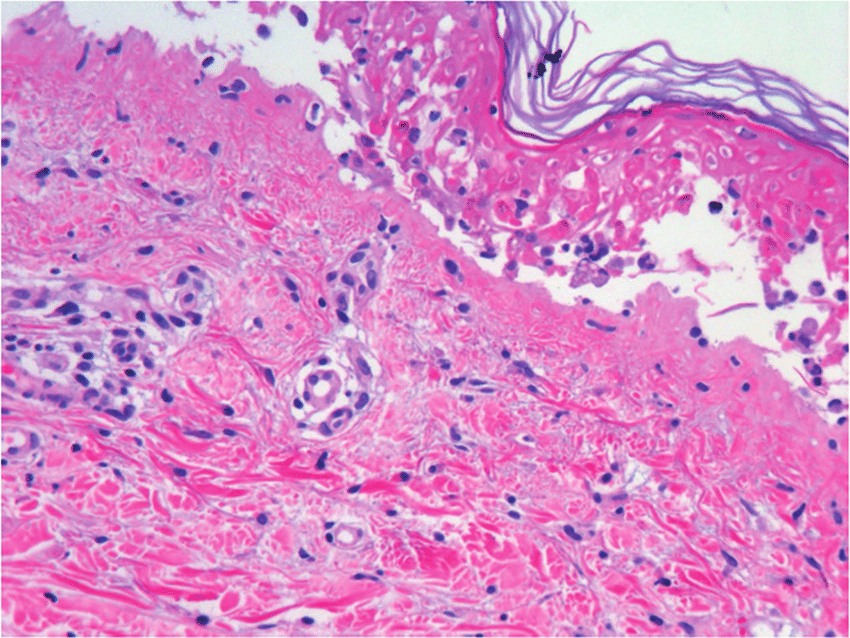

Prevalencia mundial del síndrome de Stevens-Johnson y necrólisis epidérmica tóxica asociados a antibióticos

En esta revisión sistemática y metanálisis de todas las series de casos, los antibióticos se asociaron con más de una cuarta parte de los casos de síndrome de Stevens-Johnson y la necrólisis epidérmica tóxica descritos en todo el mundo. La clase de sulfonamida se asoció con el 32 % de los casos, seguida de las penicilinas (22 %), las cefalosporinas (11 %), las fluoroquinolonas (4 %) y los macrólidos (2 %). Estos hallazgos resaltan la importancia de la administración de antibióticos, la educación y la concientización de los médicos, y sopesar la evaluación de riesgo-beneficio de la elección y duración de los antibióticos. JAMA Dermatol. 15 de febrero de 2023